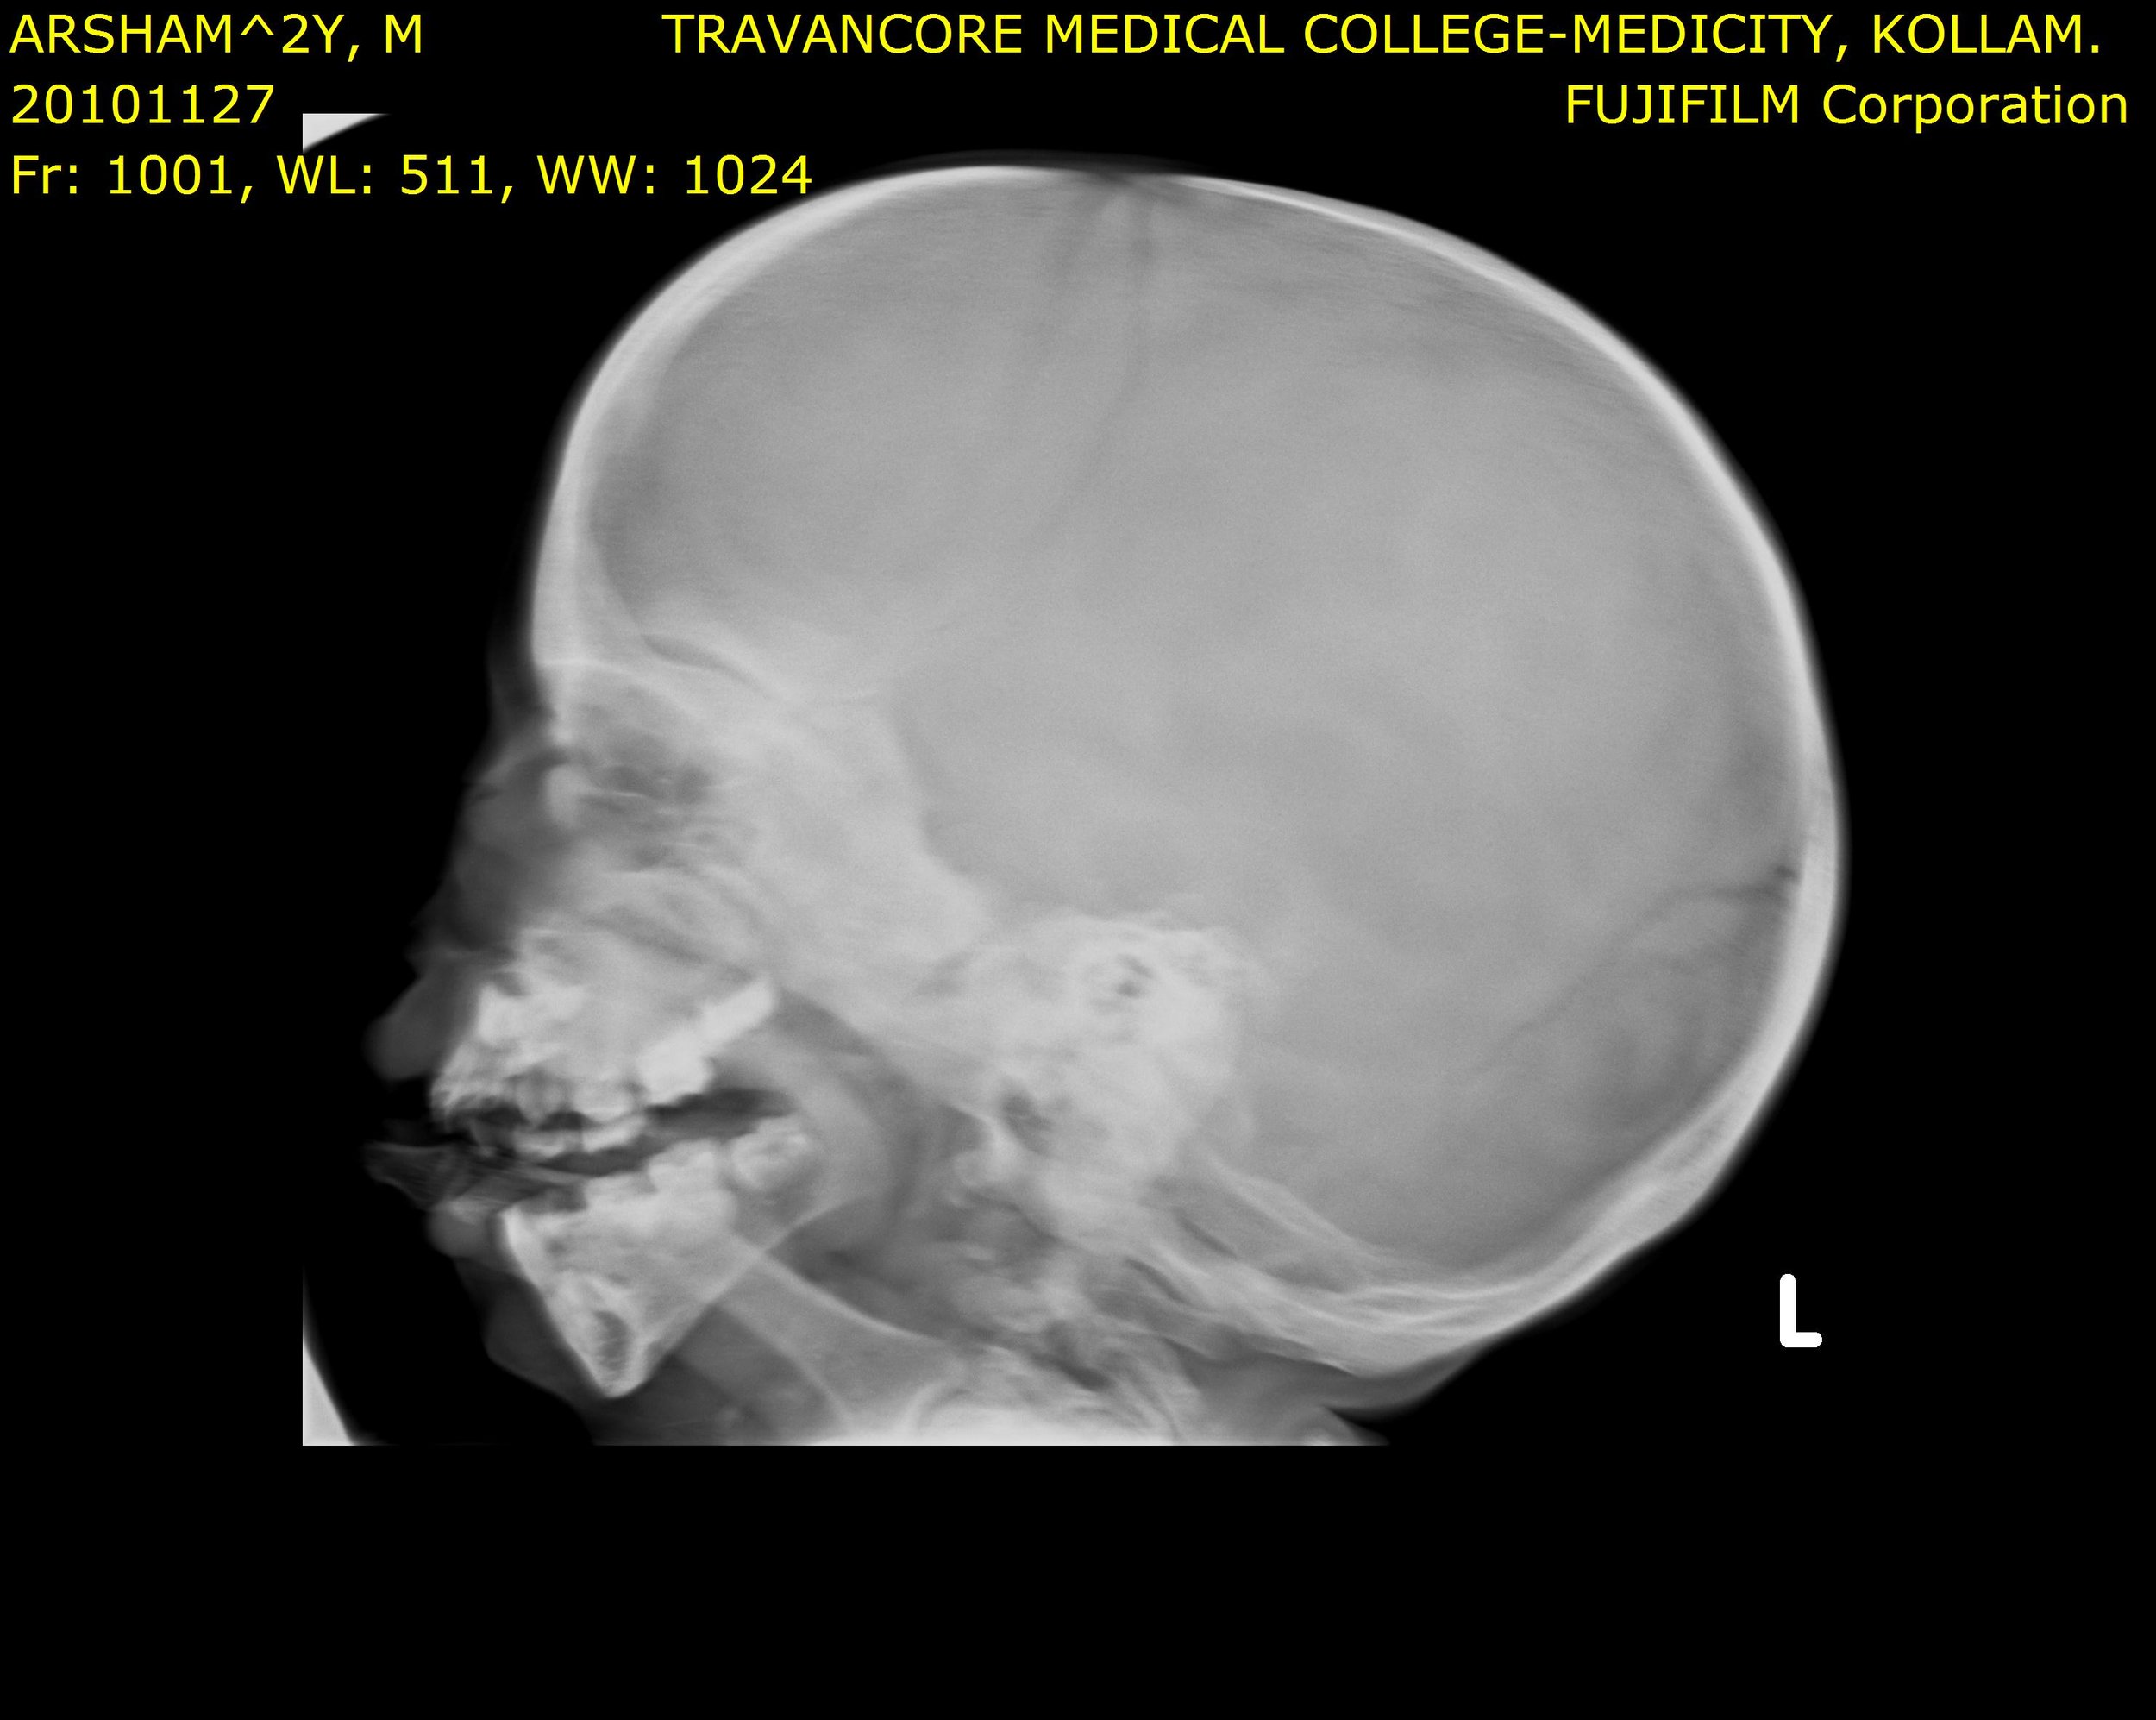

Here we share radiographic images to help with diagnosis of Jansen's disease:

Jansen's patients show extreme disorganization of the metaphyses of the long bones and of the metacarpal and metatarsal bones in sharp contrast to the almost normal appearance of the epiphyseal centers, which on x-ray appear widely separated from the long bones. The chin is receding. The fingers, especially the distal phalanges, are very short. The spine, pelvis, and lower legs are distorted.

Jansen's patients present at birth with prominent eyes, choanal stenosis, wide cranial sutures, highly arched palate, micrognathia, rib fractures, and irregularities of the metaphyses of the long bones resembling rickets. At the age of 2-3, patients show stunted growth, waddling gait, enlarged joints, prominent supraorbital ridges, and frontonasal hyperplasia.